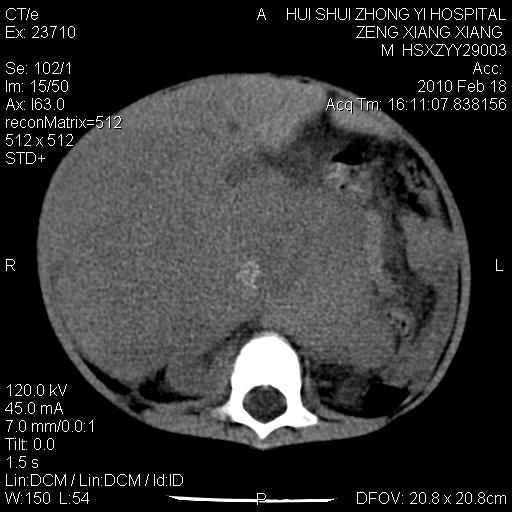

标题: PED3106:男,2岁,腹胀1月。 [打印本页]

标题: PED3106:男,2岁,腹胀1月。

定位腹膜后,肾上腺来源;

定性:恶性神经源性,肾上腺神经节母细胞瘤可能性大。

鉴别:肝母、肾母、肝脏中胚层错构瘤。

依据:年龄、有钙化,肾脏及肝脏受压移位。

肝母细胞瘤可能性大,右肾形态大体可见,不支持肾母细胞瘤,右肾移位不明显,肾上腺神经母细胞瘤可能性不大。